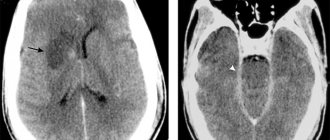

- МРТ головного мозга – демонстрирует гиперинтенсивный сигнал во фронтальных и теменных долях (в белом веществе), поражение заднего бугорка таламуса, сосудистые мальформации;